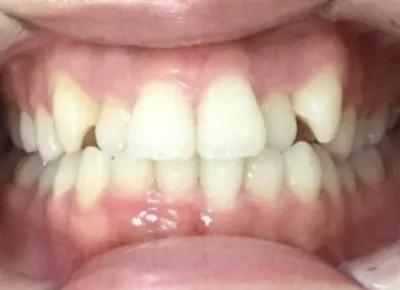

Before

After

治療期間

費用総額